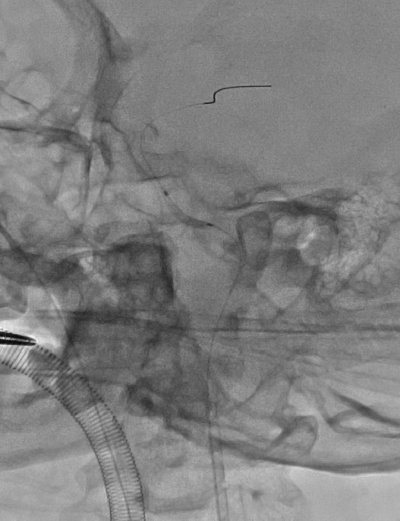

▲ 缝合左颈内动脉切口后,左颈总动脉置入鞘管、造影

▲ 支架植入后造影颈内动脉全程通畅